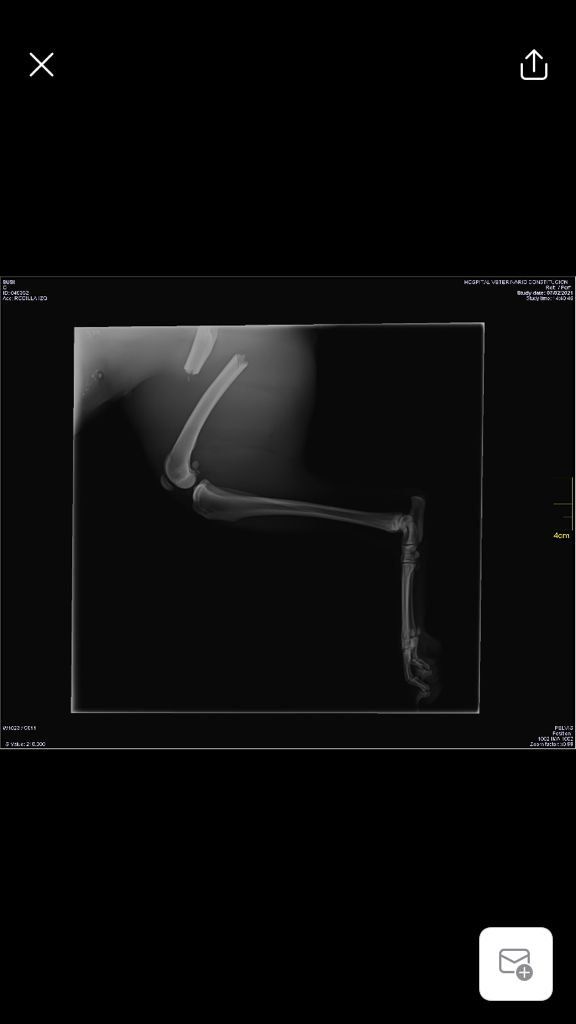

Sushy apareció atropellada en la carretera, de alli la llevaron a la perrera, donde querian sacrificarla, por suerte unas personas la sacaron y nos pidieron ayuda para ella, despues de traerla desde valencia ingreso en un hospital veterinario donde la operaron 3 veces, se paso varias semanas ingresada y cuando por fin salio a una casa de acogida se dio cuenta de que engordo en 3 dias y se le inflamaron las mamas.

Busca acogida o adopcion, el 12 de mayo la vuelven a operar y esta se supone que ya es la ultima, nos han dicho que se va a recuperar por completo.